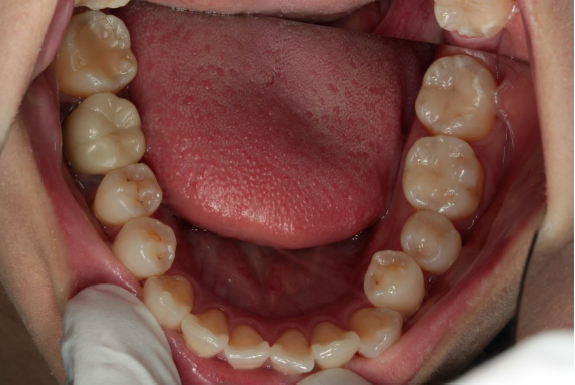

CRによるダイレクトボンディング法

左下奥歯の3本をCRにより修復しています。(保険and自由診療)

新規作成後の調整中